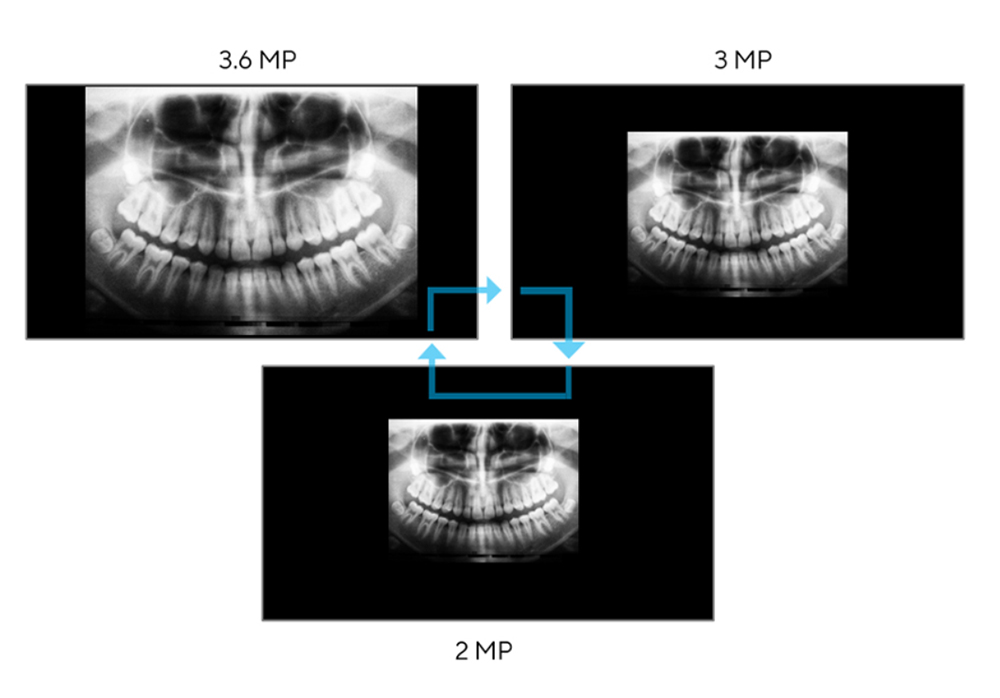

3.6mp yüksek çözünürlük

uygun ekran çözünürlüğü

farklı tıbbi görüntüleme yöntemlerinde, tıbbi görüntülerin sunumu hem boyut hem de görüntülenen bilgi miktarı açısından farklılık gösterebilir. asus healthcare monitörler, ekrandaki noktadan noktaya değişen tıbbi görsel kaynakları görüntülemek için birden fazla çözünürlük kullanabilir.